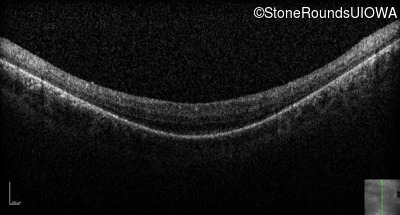

Optical Coherence Tomography - Left - 20/80 -2

Exemplar / OCT Stack

OCT Stack